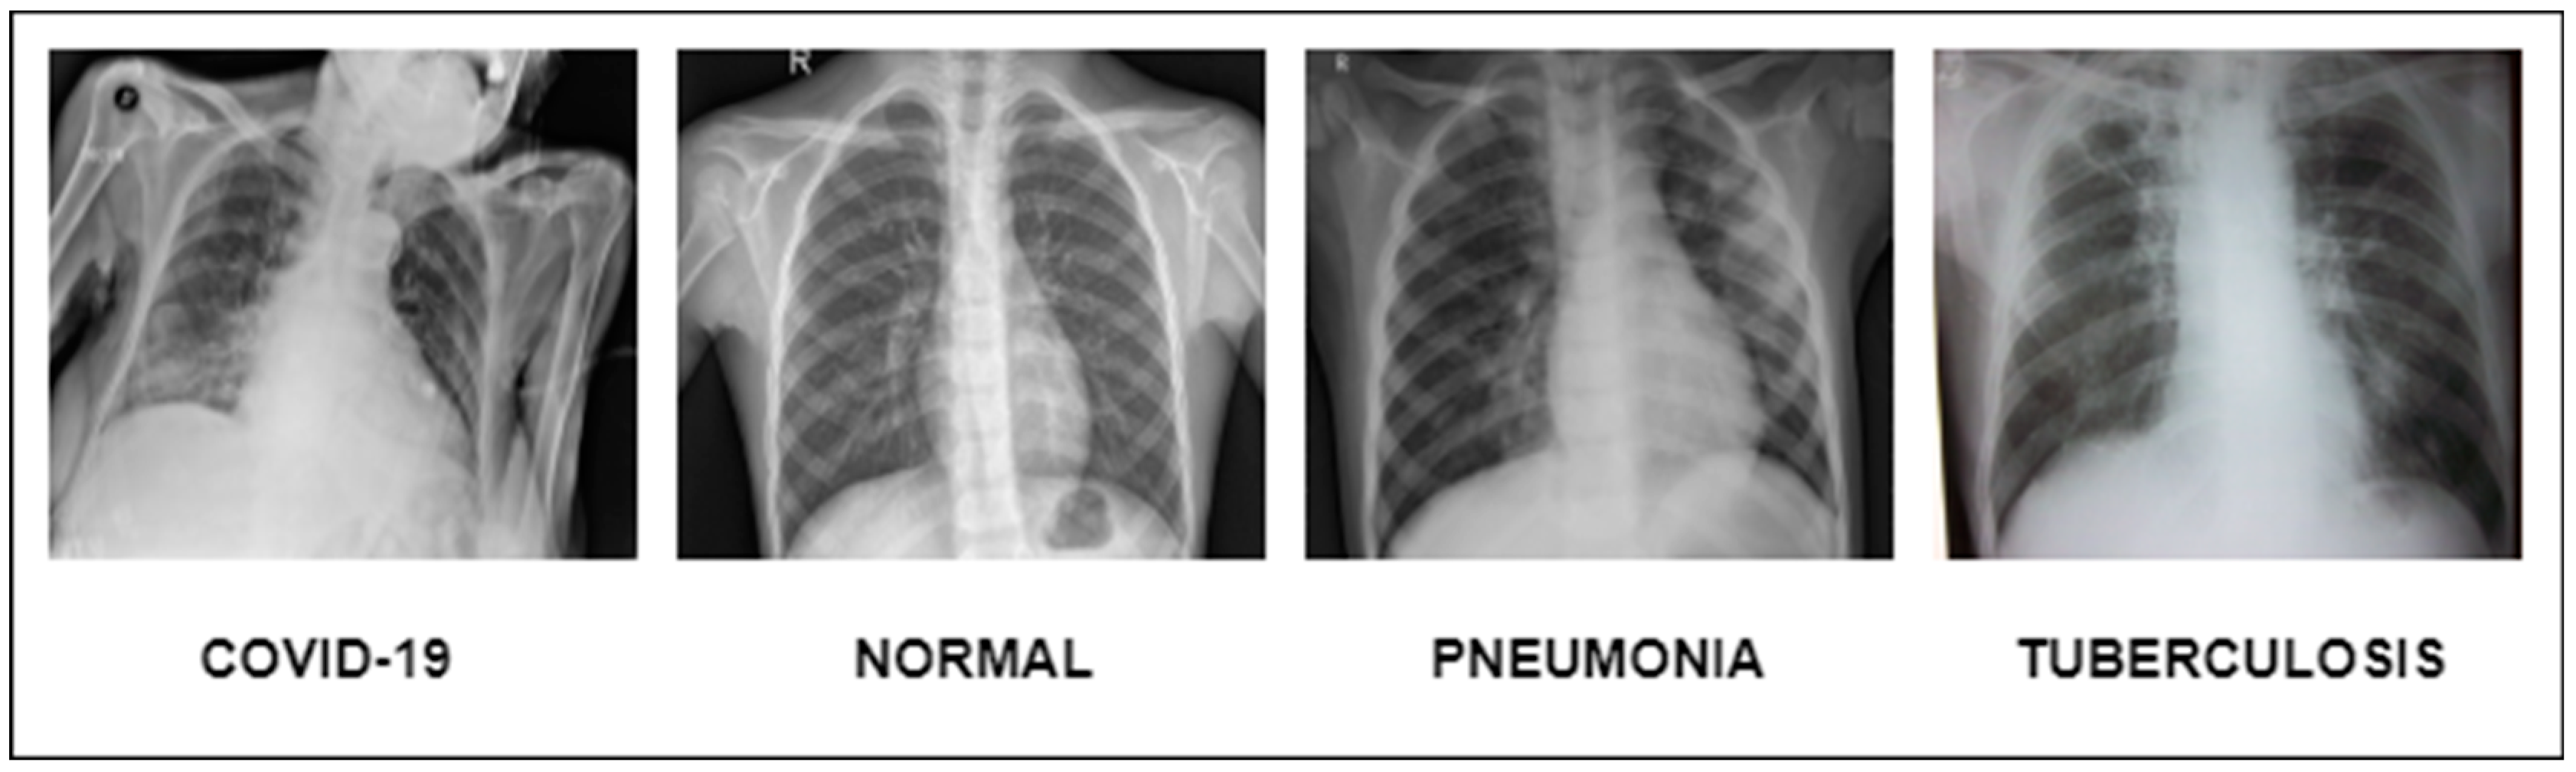

This extensive study gives important insights into the creation of DL models for the identification of pneumonia, TB, COVID-19, and lung cancer. They show how DL can reliably detect and categorize lung disorders, resulting in improved patient outcomes and more effective healthcare administration, as shown in Figure 1. We want to use the advances provided in these studies, as well as other relevant research, to construct a complete DL model for lung illness recognition and classification in this work. Our study aims to improve the accuracy, efficiency, and consistency of lung illness detection by analyzing varied datasets and applying cutting-edge approaches, ultimately leading to better patient care and treatment.

Meticulously inspected 13,313 lung photographs are shown in Figure 1. The three datasets that were used to build the training and testing fundus sets, each with a distinct dimension setting, are broken down in Table 3 and Table 4. All photos used in the experiment were downsized to 700 × 600 pixels, after which they were processed to create binary labels. A total of 13,313 photos made up the whole dataset, of which 3993 were used to evaluate the system. To guarantee neutrality, the dataset was initially converted into different classes by balancing the overall dataset number of photos both during and after the illness. Before being put into an algorithm created especially for the MixNet-LD model, the photos underwent pre-processing by being resized to 700 × 600 pixels. To lessen the variation between data points, the photos were also standardized. Data from Pak-Lungs is also used to train and assess the MixNet-LD system. Each image was initially saved with a resolution of 1125 × 1264 pixels.